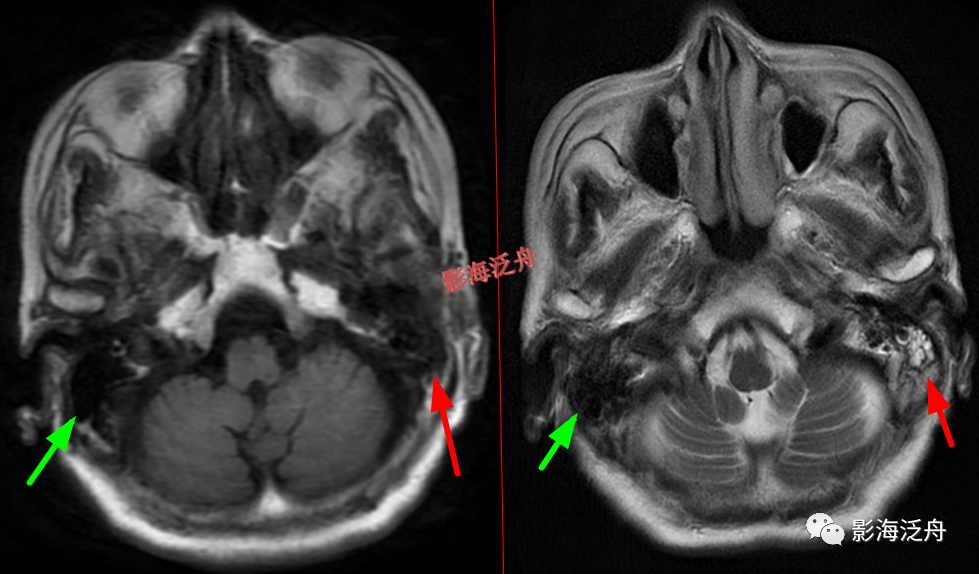

颞极前方蛛网膜囊肿(红箭)漏诊率也比较高,尤其在老年患者中,常常被误认为是扩大的蛛网膜下间隙,仔细观察可以发现右侧颞叶受压,脑沟闭塞(绿箭),与健侧(蓝箭)对比更为明显。